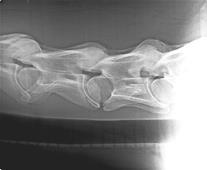

Besonders wichtig erscheinen auch Veränderungen im Bereich des 6. und 7. Halswirbels sowie des ersten Brustwirbels. Dieser Bereich konnte früher nur ungenau und in Vollnarkose dargestellt werden.

Mit der Verfeinerung der Röntgentechnik erreichen wir für diesen Bereich aussagekräftige Bilder im Stehen bei normaler Sedation.

Wir wundern uns immer wieder, wie viele krankhafte Veränderungen hier zu finden sind, die die Pferdemedizin früher auf Grund nicht so guter Technik übersehen hat.